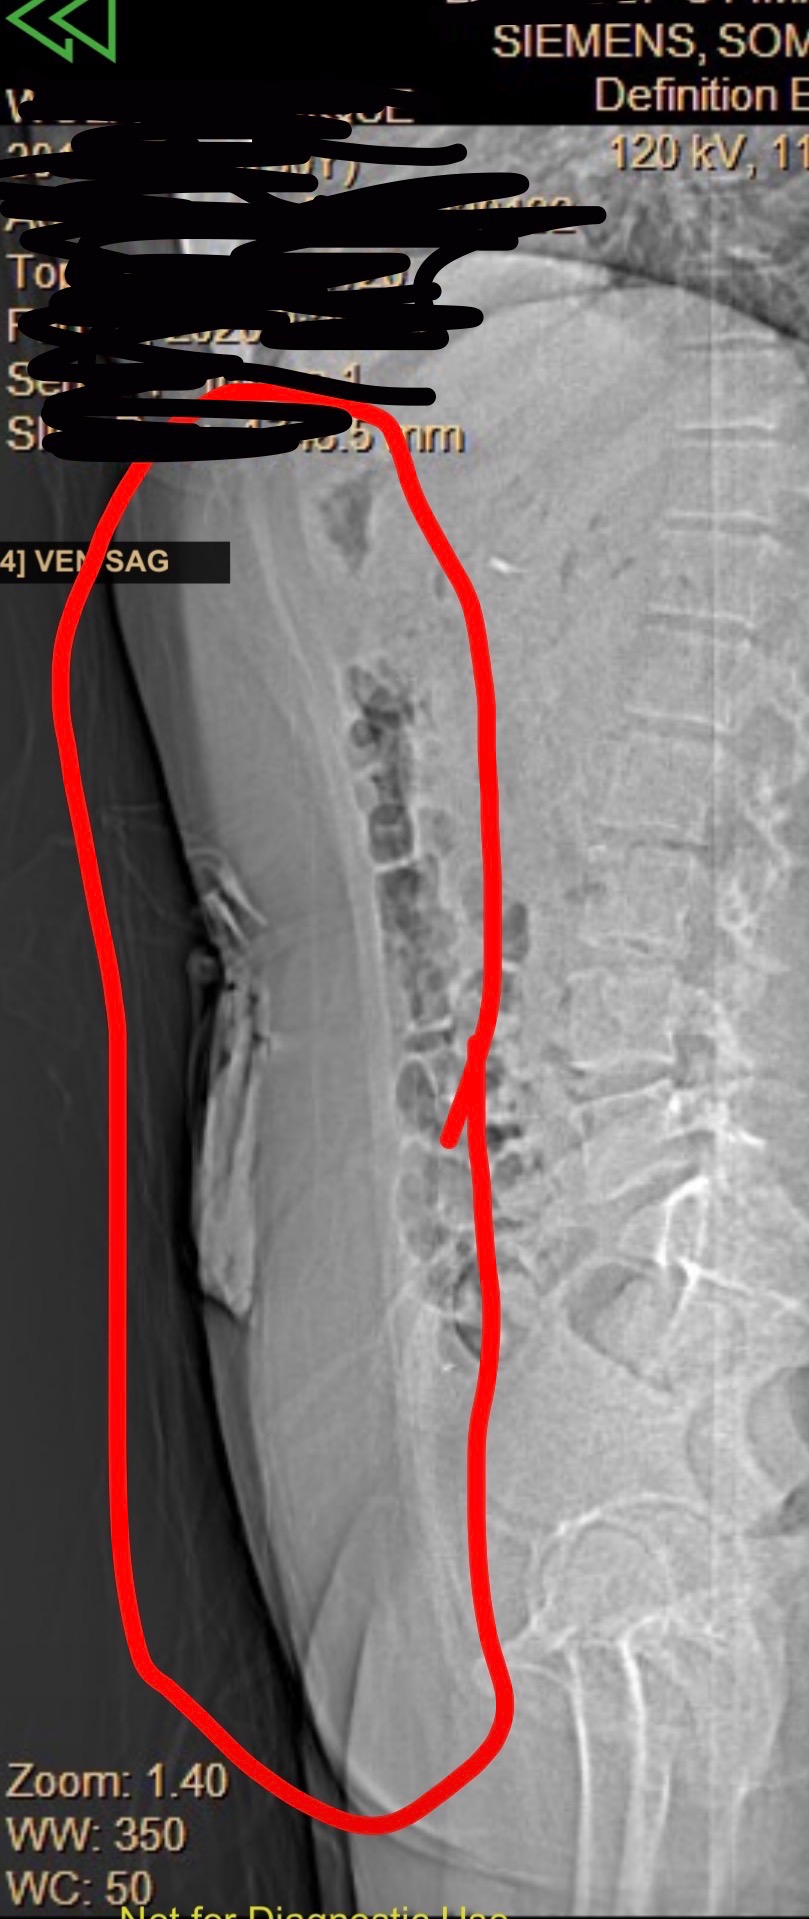

I was admitted right away. Doctors confirmed that I was severely dehydrated and malnourished and told my husband that if he hadn’t acted when he did, the outcome could have been life-threatening. I underwent surgery for an emergency endoscopy and feeding tube placement, followed by additional procedures, including injections to help my stomach function properly. More invasive surgeries are still a possibility if my body doesn’t respond to treatment.